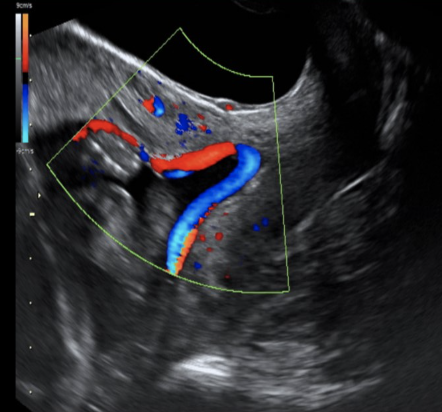

which intracranial anomalies is most commonly assoc w/fetal hydrops, ascites, and congestive heart failure

a) schizencephaly

b) holoprosencephaly

c) intracranial bleed

d) vein of galen aneurysm